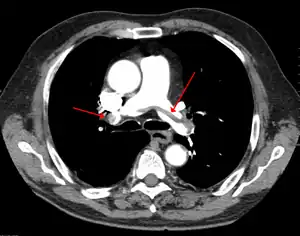

Chest spiral CT scan with radiocontrast agent showing multiple filling defects both at the bifurcation ("saddle" pulmonary embolism) and in the pulmonary arteries

Large saddle embolus seen in the pulmonary artery (white arrows).